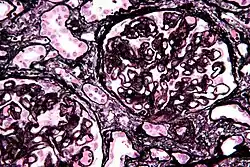

| Micrograph of membranous nephropathy showing prominent glomerular basement membrane spikes. Jones' stain. | |

- By light microscopy, the basement membrane is observed to be diffusely thickened. Using Jones' stain, the GBM appears to have a "spiked" or "holey" appearance.